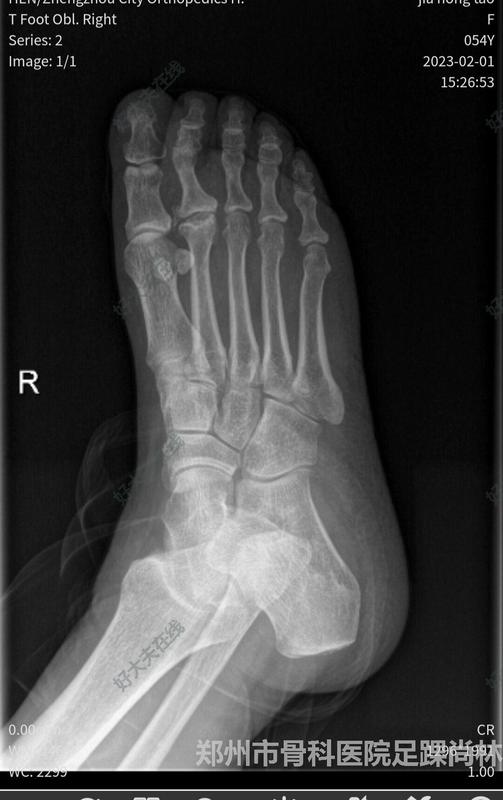

Freiberg病

一例特殊病例总结(药物引起的骨折疏松)